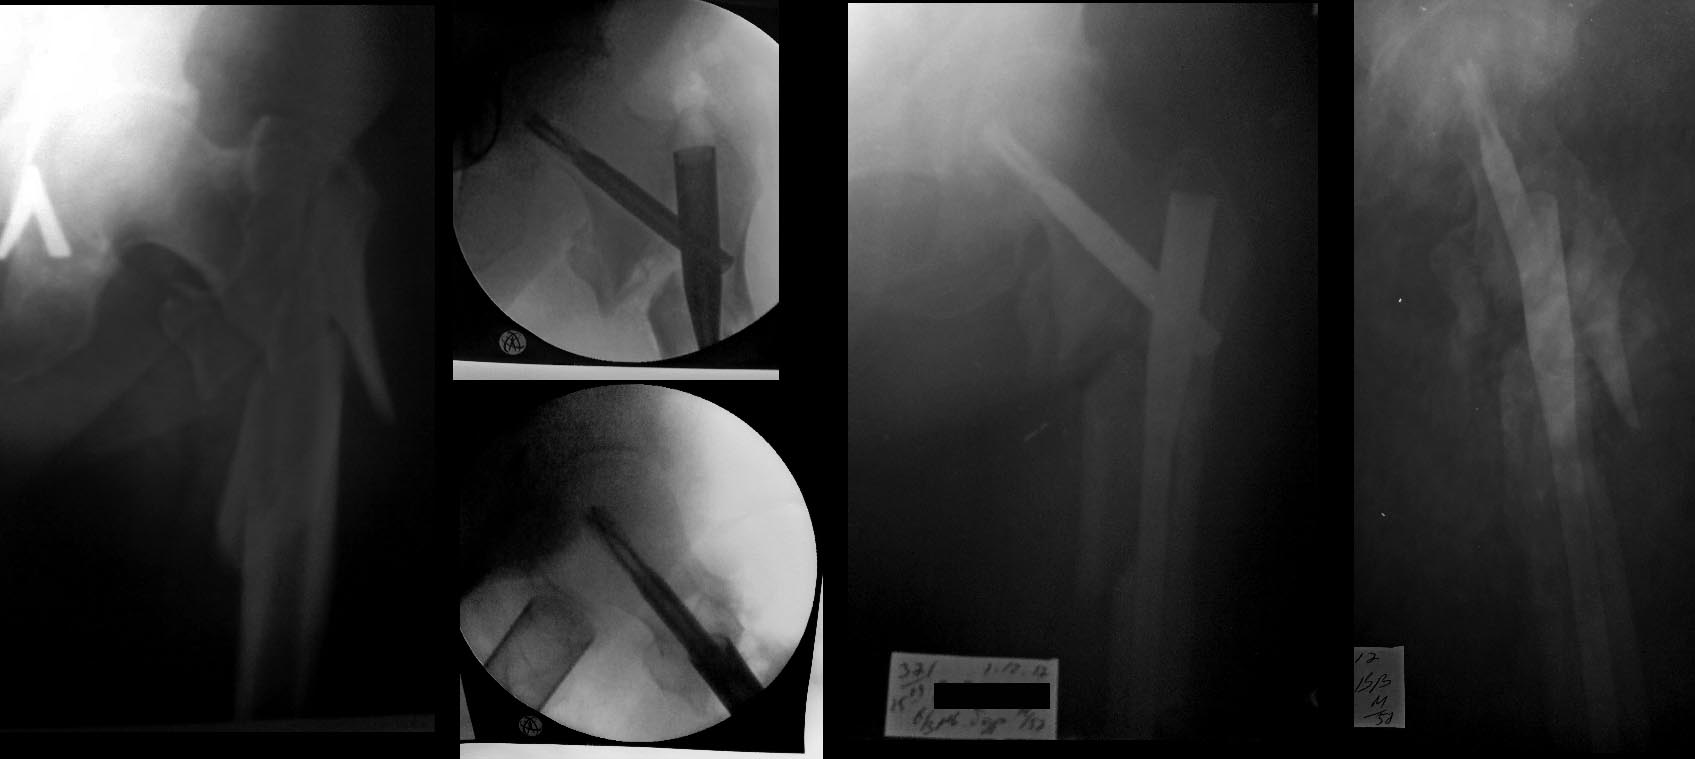

Пациент 57 лет повышенного питания ок.110-115 кг.соматически здоров,

оперирован 1.12.17.-закрыто БИОС PFN-a long,(имплант без возможности

первичной компрессии),имеется удлинение конечности на 2,3-3 см.Какова

программама реабилитации и нагрузки в данной ситуации уместна? Спасибо